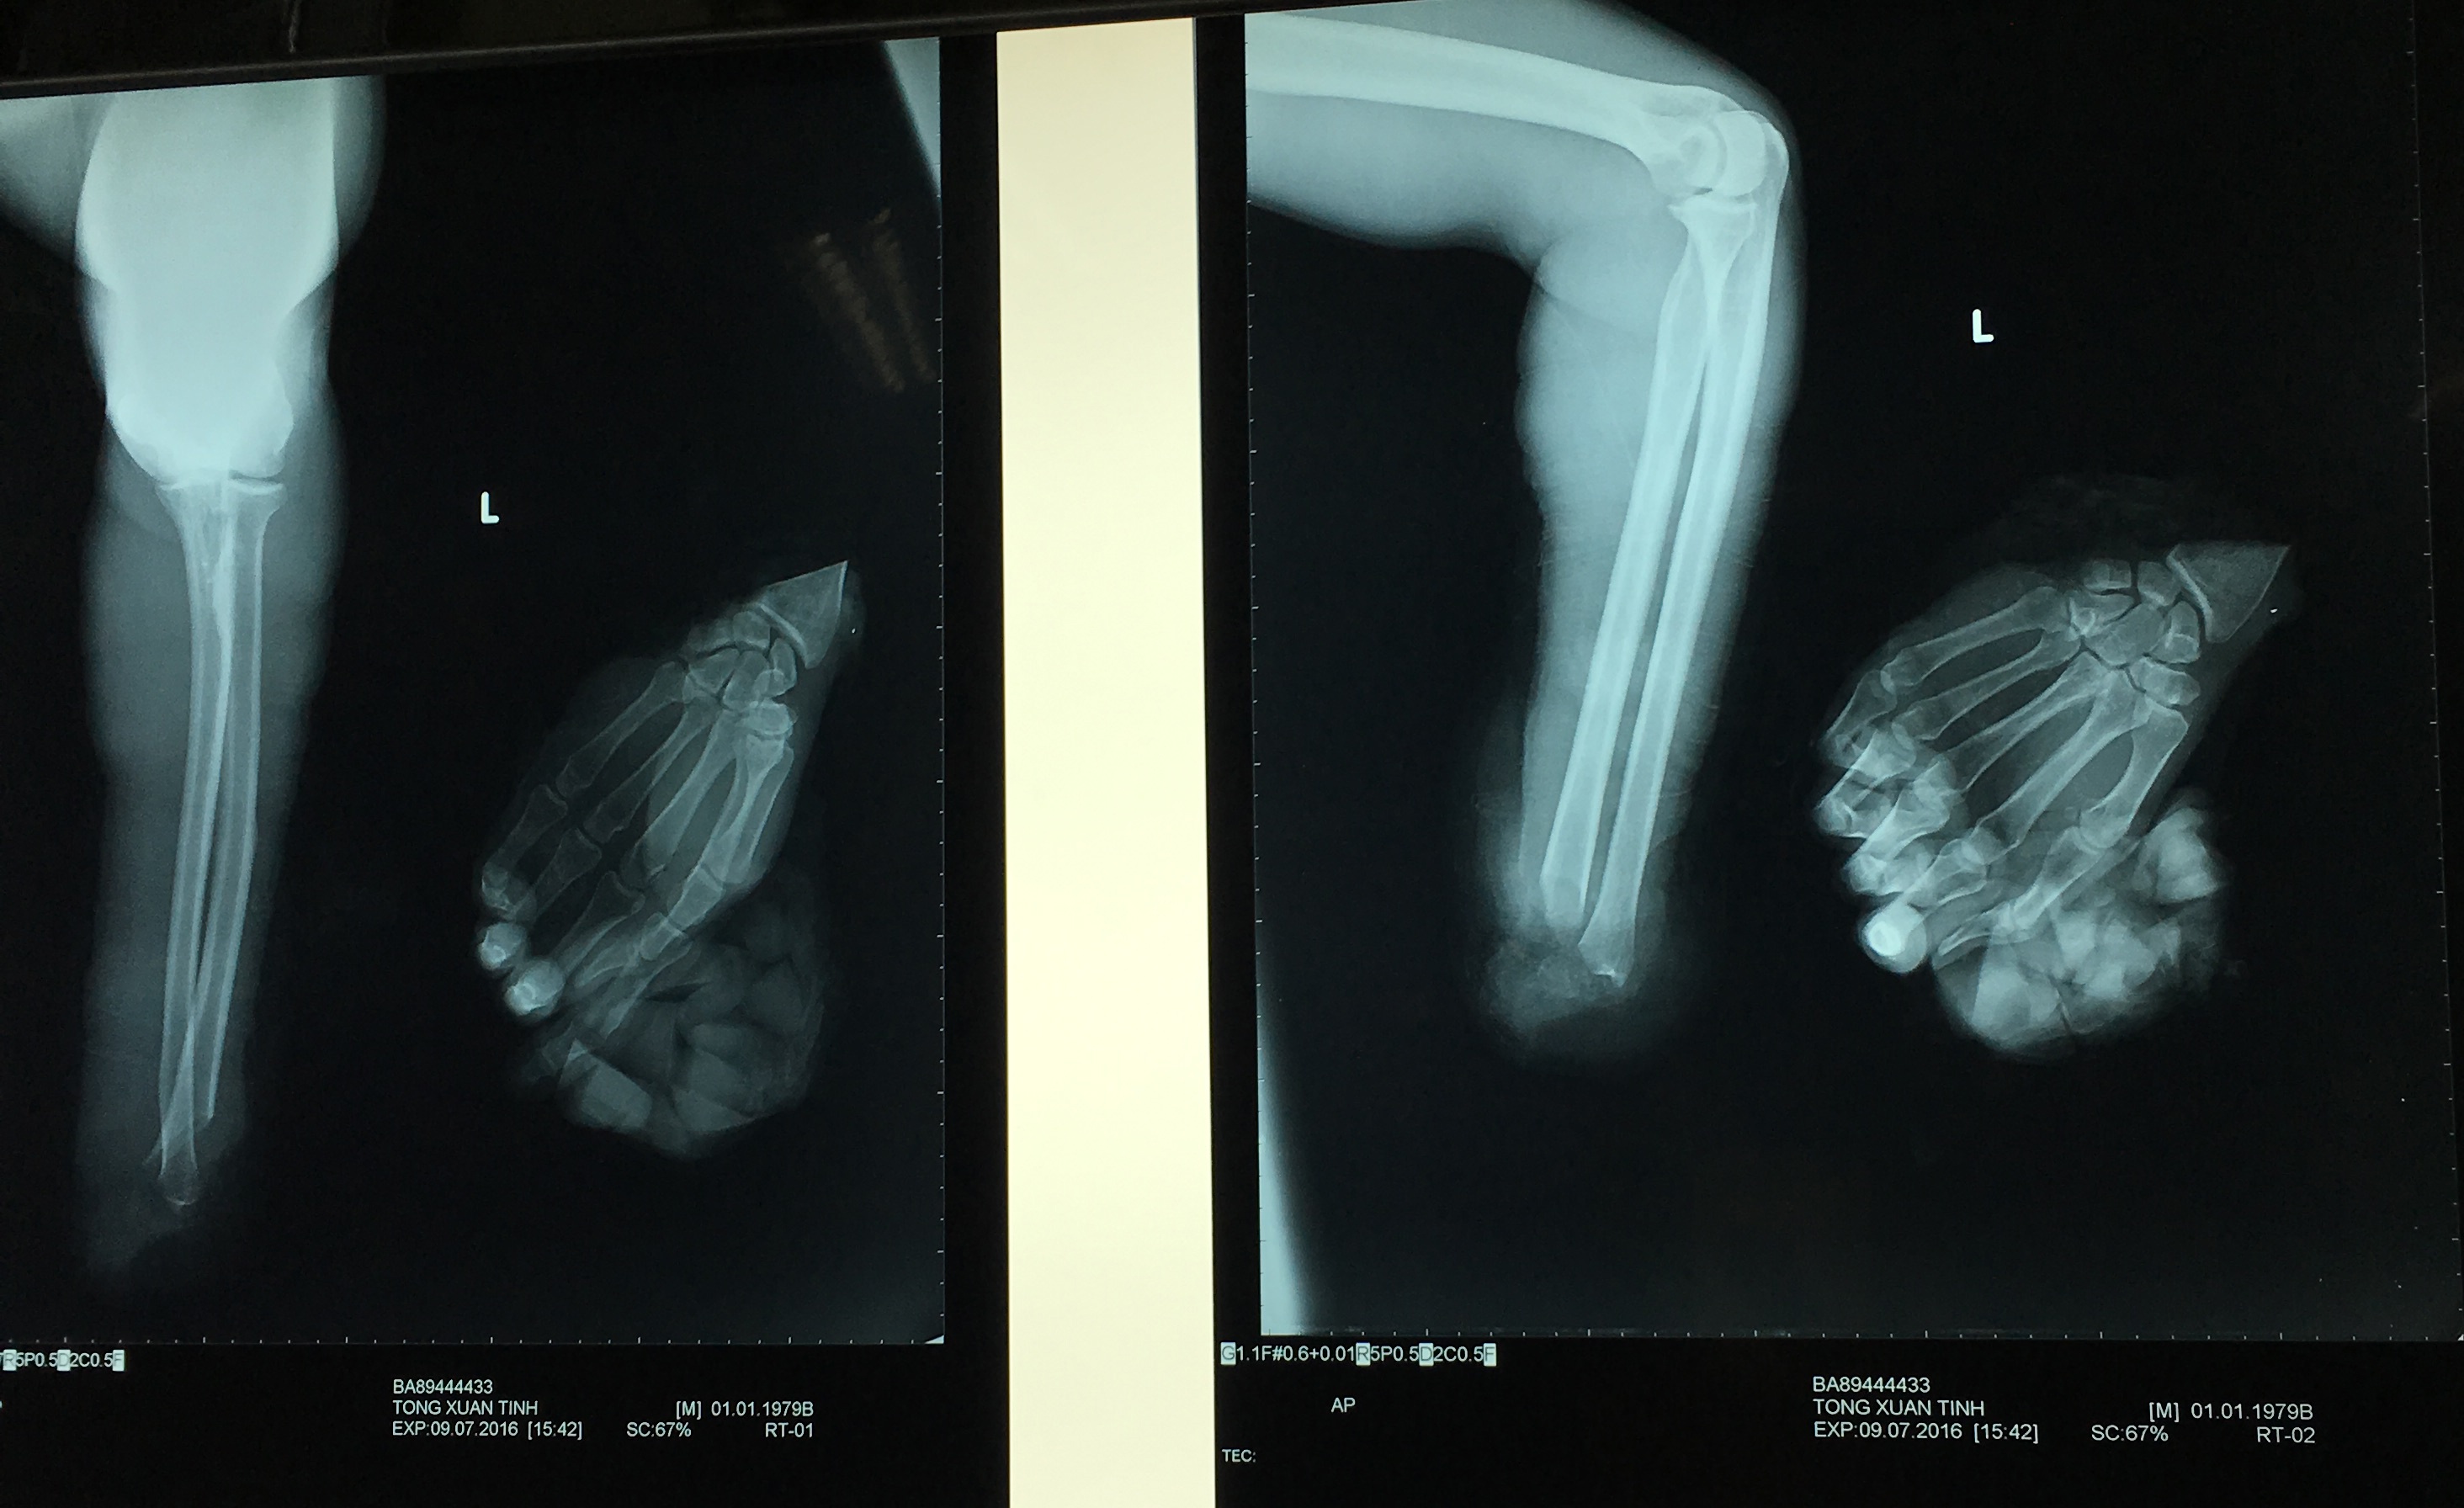

| Phim chụp X-quang cánh tay bị đứt lìa của anh Kỳ. Ảnh: Bệnh viện cung cấp. |